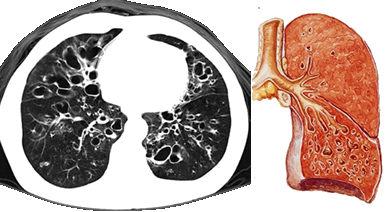

是指各種原因?qū)е碌闹夤芙Y(jié)構(gòu)破壞,引起支氣管異常和持久性擴(kuò)張。

支氣管擴(kuò)張大多繼發(fā)于急、慢性呼吸道感染和支氣管阻塞。